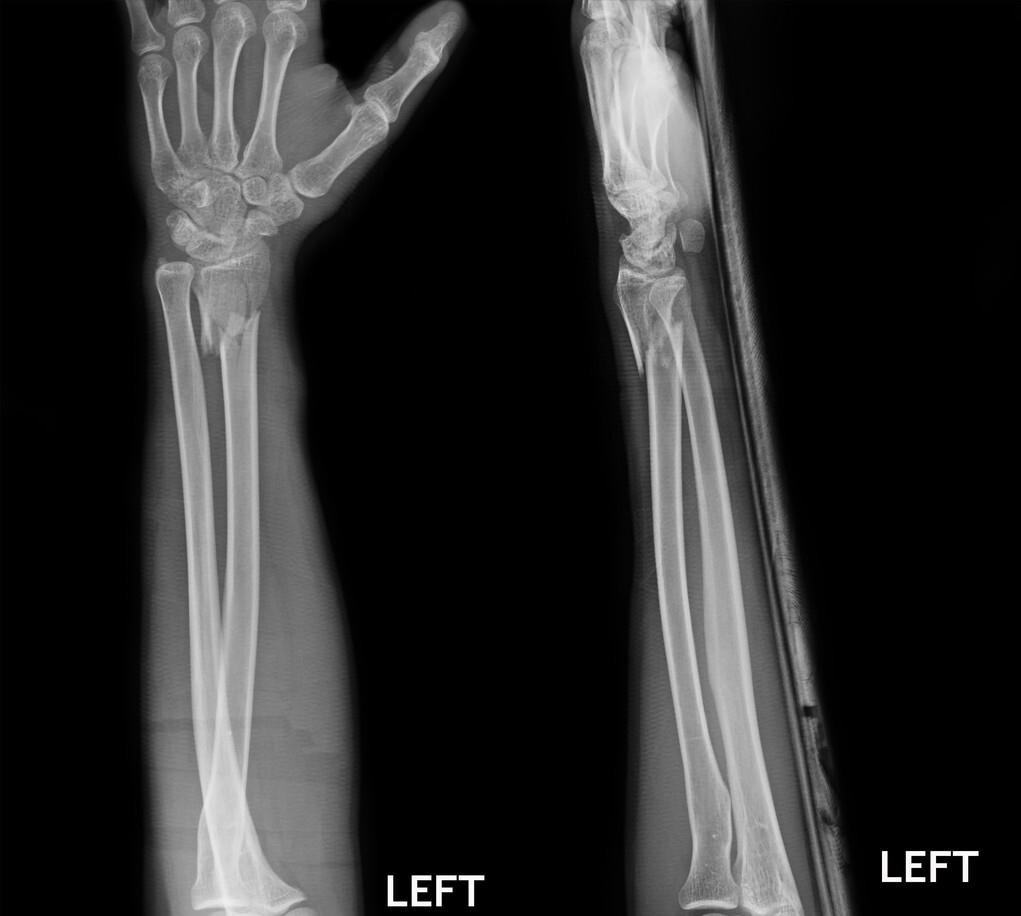

三十多岁的一个女性,前臂桡骨靠近手腕的部位骨折了。

是因为骑电动车时,前面急刹车,她跟着紧急刹车,摔倒了,手掌撑地,手腕部就肿起来了。

赶快到医院看吧,片子一拍,桡骨远端骨折。